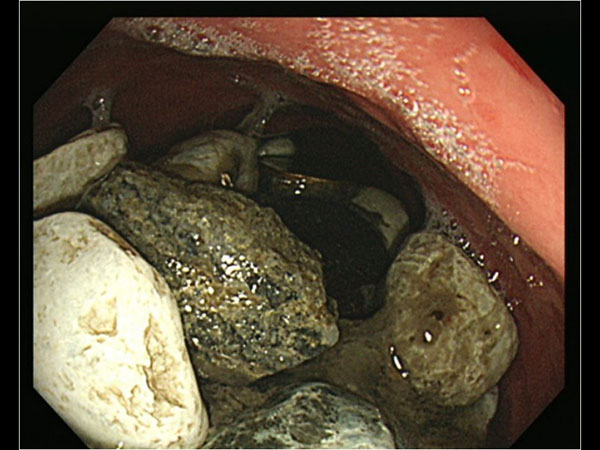

കല്ല്, അടപ്പ്,നാണയം; വയറ്റിലായത് 2 കിലോയോളം

കല്ല്, നാണയം,കുപ്പിയുടെ അടപ്പ്, മണ്ണ് എന്നിവയൊക്കെ കഴിക്കുന്നതിനെപ്പറ്റി നമുക്ക് ചിന്തിക്കാന് പോലും സാധിക്കുകയില്ല. എന്നാല് ഉത്കണ്ഠ എന്ന പ്രശ്നത്തെ മറികടക്കുന്നതിന് വേണ്ടി ഇത്തരത്തില് ചില വസ്തുക്കള് പലരും അകത്താക്കുന്നുണ്ട്. ഇത് പല വിധത്തിലുള്ള പ്രശ്നങ്ങളാണ് ഉണ്ടാക്കുന്നത്. പലപ്പോഴും ആരോഗ്യത്തിന് വില്ലനാവുന്ന അവസ്ഥ പലരിലും ഇത് ഉണ്ടാക്കുന്നുണ്ട്. എന്തൊക്കെയാണ് ഇത്തരത്തില് ഒരാള് കഴിച്ചത് എന്ന് നോക്കാം.

വിശദമായ പരിശോധനക്ക് ശേഷമാണ് ഇദ്ദേഹത്തിന്റെ ഈ സ്വഭാവത്തെക്കുറിച്ച് പുറത്തറിഞ്ഞത്. വയറില് പരിശോധിക്കുമ്പോള് കല്ല് പോലെ തടയുന്നത് പോലെ പരിശോധനയില് അനുഭവപ്പെട്ടു. പരിശോധന ഫലമാണ് ഞെട്ടിച്ചത്. ഇദ്ദേഹത്തിന്റെ വയറ്റില് നിറയെ ഇത്തരത്തിലുള്ള കല്ലുകളാണ് എന്നത് എല്ലാവരേയും ഞെട്ടിച്ചു.

എന്തുകൊണ്ട് വയറ്റില് ഇത്തരത്തില് കല്ല് പോലുള്ള ഭാഗങ്ങള് കാണപ്പെട്ടു എന്നതിന്റെ വിശദാംശങ്ങള് അന്വേഷിച്ചപ്പോഴാണ് ഇദ്ദേഹം കാലം കുറേയായി ഉത്കണ്ഠ പോലുള്ള അവസ്ഥകള് വന്നാല് ഇത്തരത്തില് കല്ലും കുപ്പിയുടെ അടപ്പും നാണയങ്ങളും ആണ് കഴിക്കുക എന്നാണ് പറയുന്നത്. ഇത് ലഹരി കഴിക്കുന്നത് പോലുള്ള സുഖമാണത്രേ ഇയാള്ക്ക് നല്കുന്നത്.

വായില് കൂടി ഒരു കനം കുറഞ്ഞ ട്യൂബ് വയറ്റിലേക്ക് ഇറക്കി വ്യത്യസ്തമായ ഒരു സര്ജറിയാണ് ഇയാളുടെ വയറ്റില് നിന്ന് ഇതെല്ലാം നീക്കം ചെയ്യുന്നതിന് വേണ്ടി ചെയ്തത്. അല്പം പാടു നിറഞ്ഞ ശസ്ത്രക്രിയ ആയതു കൊണ്ട് തന്നെ വളരെയധികം ശ്രദ്ധിച്ചാണ് ഇത്തരത്തില് ഒരു ശസ്ത്രക്രിയ ചെയ്തത്.